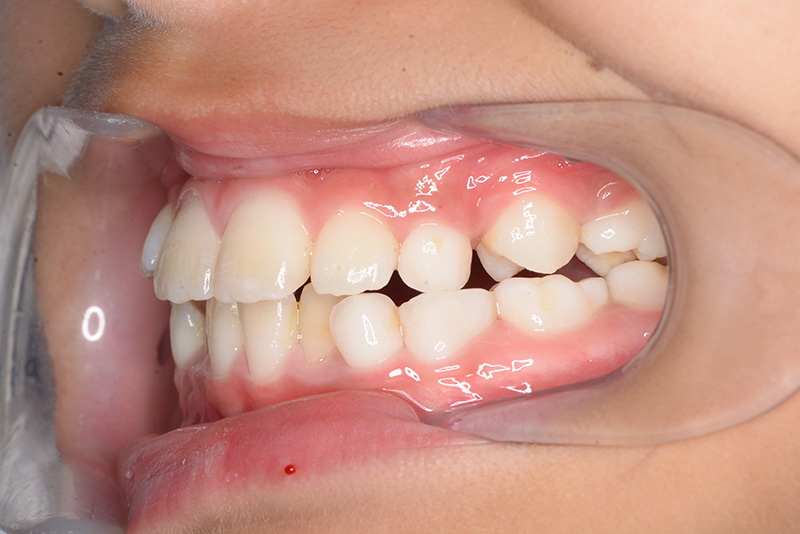

| 主訴 | 上顎6の近心傾斜、5萌出部位不足 | 診断名 | アングルⅡ級叢生症例 | ||||

|---|---|---|---|---|---|---|---|

| 初診時年齢 | 8歳9ヵ月 | 性別 | 女 | 動的治療期間 | 4ヵ月 | ||

| 顔貌所見 | 正貌はほぼ左右対称。側貌はstraight type、引き締まった口唇形態をしていた。 |

| 口腔内所見 | over jet 2.5mm、over bite 2.0mm、右側大臼歯関係はEnd on class Ⅱ、上顎左側Eは早期喪失により左側大臼歯関係はFull classⅡ、右側Eは6の異所萌出により歯根吸収が進行したため一般歯科医院にて抜去済みであった。 |